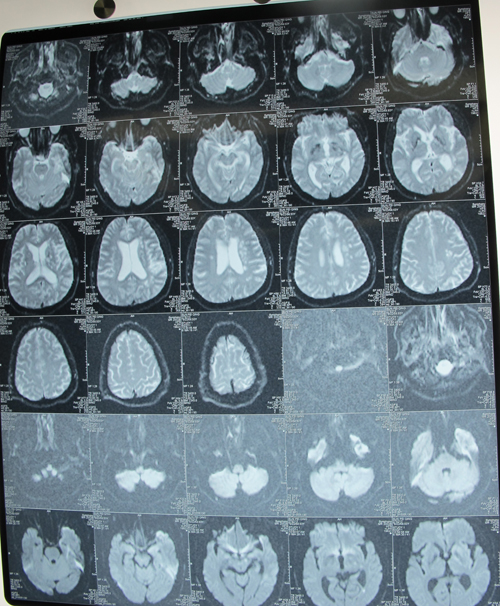

头颅MRI示(2011-5-28,大同市三院):左侧颞叶大面积脑梗塞。

颈动脉血管超声示:双侧颈总动脉粥样斑块形成,左侧颈内动脉软斑,重度狭窄,狭窄率约81%。

头颈部CTA示左侧颈内动脉闭塞。